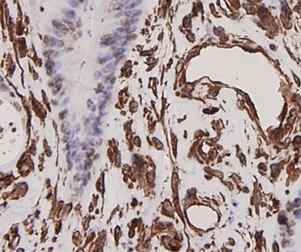

ApplicationsFlow Cytometry, Western Blot, ImmunoCytoChemistry, ImmunoHistoChemistry

- ApplicationsFlow Cytometry, Western Blot, ImmunoCytoChemistry, ImmunoHistoChemistry